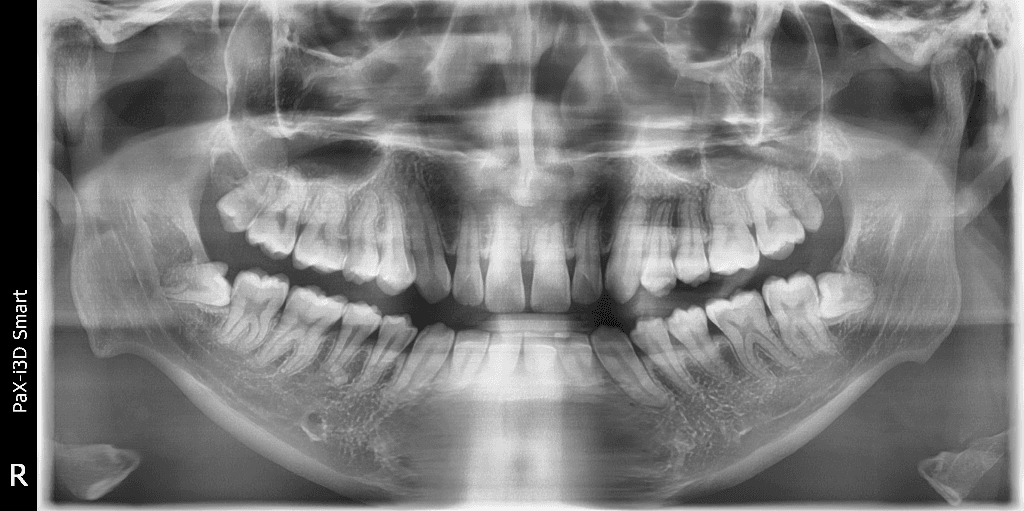

현재 사랑니에 충치가 발생한 것으로 보이며, 이 경우 사랑니를 발치하길 권합니다. 따라서 정확한 상태 확인을 위해 치과 진료를 받길 권합니다.

사랑니가 잇몸 밖으로 튀어나오면서 생긴 것으로 보이며 사랑니가 좋지 않으니 발치 하는 게 좋겠습니다.

부분 맹출된 사랑니에 음식물이 자주 끼고 구강위생관리가 되지 않아 충치가 생긴 것으로 보입니다. 가끔 통증을 일으키는 것은 사랑니 치아머리 주위의 잇몸에서 염증이 발생하는 치관주위염 때문일 수 있습니다. 치과에서 검진받으시고 사랑니 발치하는 것을 권유드립니다.

방사선 사진상 사랑니가 충치가 생긴 것 같지는 않으나 해당 부위 사랑니의 부분 매복으로 인해 잇몸이 벌어져 있고 잇몸도 부어있는 상태입니다.

부분 매복 사랑니는 향후 문제를 일으킬 여지가 많으므로 예방적으로 발치를 권합니다.

사진으로 봤을 경우에는 사랑니가 부분적으로 맹출되고 있는 것으로 보입니다. 사랑니가 기울어져 나있을 경우 해당 부위에 이물질이 끼게 되어 주변 조직에 염증이나 충치를 일으켜 발치를 해주는 것이 좋을 수 있습니다.